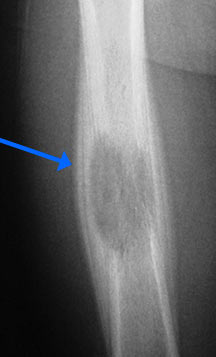

- May arise from any bone and any site within a bone (epiphyseal, metaphyseal, diaphyseal)

- Radiographically variable appearance: may appear benign (geographic) or malignant (permeative or moth eaten)

- Humerus